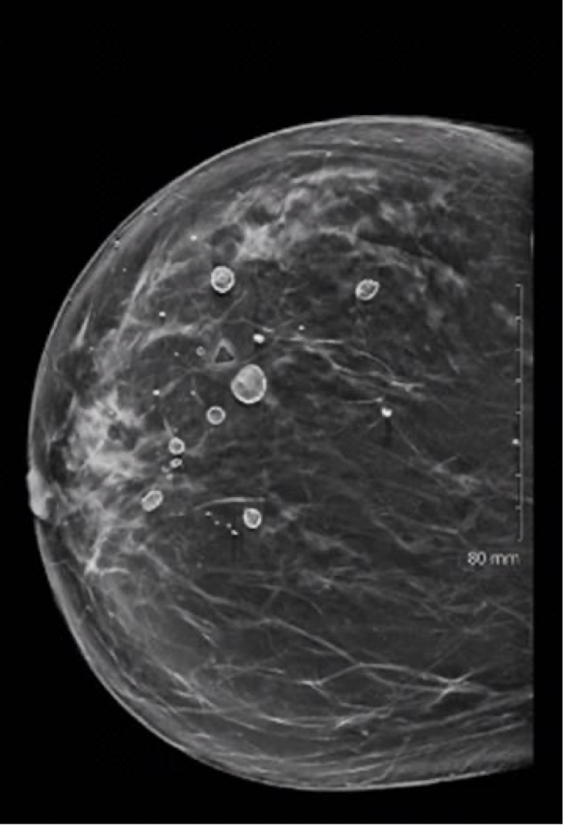

MAMMO SONO for FCC

micro calcifications and multiple round masses

FCC (fibrocystic condition)